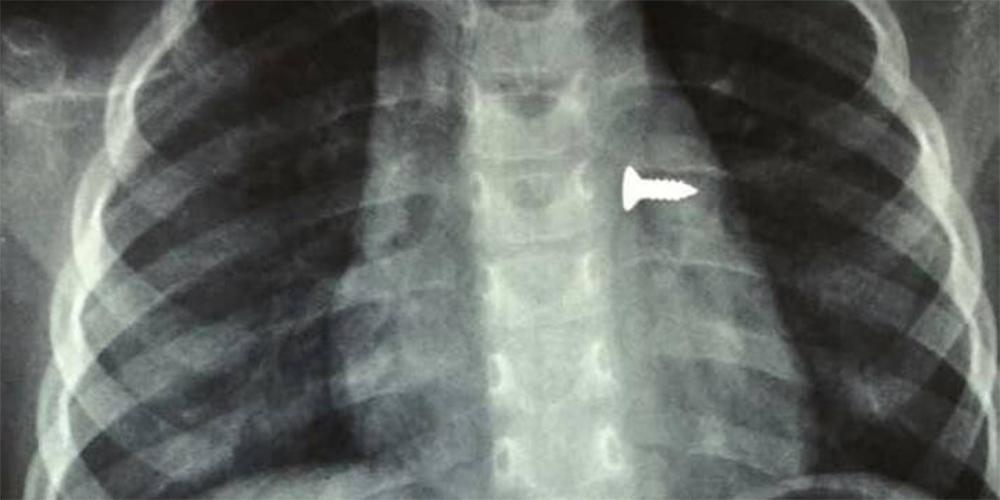

Σύμφωνα με τα όσα έκανε γνωστά ο αναπληρωτής καθηγητής ΩΡΛ της Ιατρικής Σχολής Κρήτης, Μανώλης Προκοπάκης, το παιδί μεταφέρθηκε στο νοσοκομείο και αμέσως του έγιναν ακτινογραφίες που έδειξαν πού βρισκόταν η βίδα σύμφωνα με το cretapost.gr.

Οι γιατροί άμεσα οδήγησαν το κορίτσι στο χειρουργείο και μετά από αρκετή ώρα κατάφεραν να αφαιρέσουν την βίδα. Ο κ. Προκοπάκης σε ανάρτησή του στα social media ανέφερε: «Πολύ επείγον χειρουργείο! Πριν από λίγο. Αφαίρεση βίδας από αριστερό βρογχικό δέντρο τρίχρονου κοριτσιού. Πολύ επικίνδυνο…».